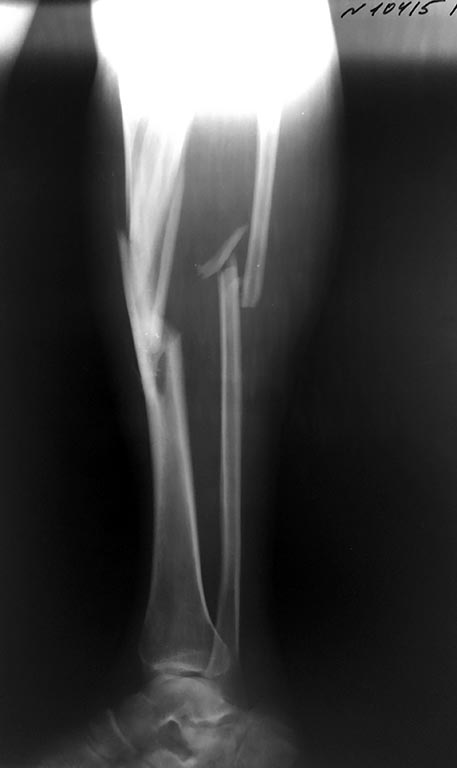

[Ortho] Перипротезный перелом бедра и перелом костей голени

Здравствуйте!Пациент М 54 года. 25.05.2015 г. в результате ДТП получает

сочетанную травму.

Снимки прилагаются. Интересно ваше мнение по тактике лечения данного

пациента. Есть многочисленные металлоконструкции и технологии

оперативных вмешательств.